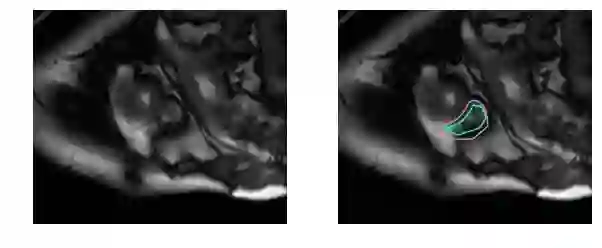

而对于未训练过的肉眼,右心室区域是这样的: